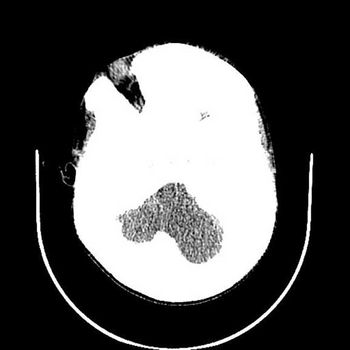

Case History: A 28-year-old man presented with history of pulsing noise in the head and progressive right hemiparesis.